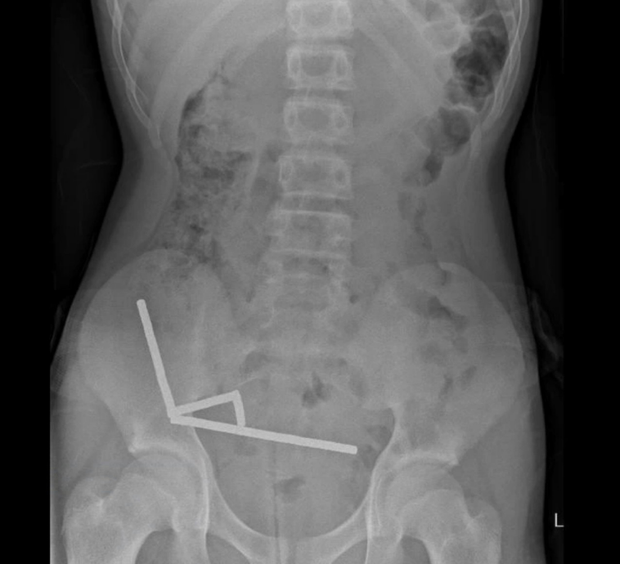

Scans showed that the magnets had linked into four chains inside the teen’s bowel and at the start of his large intestine. The amount of magnets in his body disrupted some imaging, the report said, so doctors proceeded with an exploratory surgery.

During the operation, surgeons found the magnet chains were causing pressure necrosis in the bowel and large intestine. Pressure necrosis occurs when tissue dies because there is too much pressure on it for an extended period of time. The surgeons were able to successfully remove the magnets, and the boy recovered from the operation. He was discharged after eight days in the hospital, the report said.